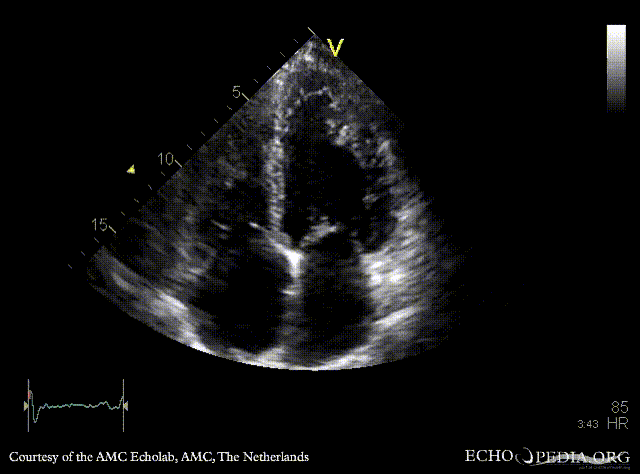

Tenting of mitral valve

PLAX: dilated left ventricle, poor function, tenting of mitral valve PLAX with Color Doppler: severe mitral valve regurgitation